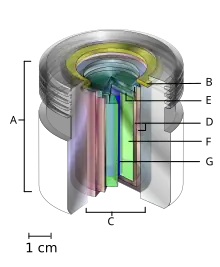

Conventional external beam radiation therapy

- an international standard source holder (usually lead),

- a retaining ring, and

- a teletherapy "source" composed of

- two nested stainless steel canisters welded to

- two stainless steel lids surrounding

- a protective internal shield (usually uranium metal or a tungsten alloy) and

- a cylinder of radioactive source material, often but not always cobalt-60. The diameter of the "source" is 30 mm.

Historically conventional external beam radiation therapy (2DXRT) was delivered via two-dimensional beams using kilovoltage therapy X-ray units, medical linear accelerators that generate high-energy X-rays, or with machines that were similar to a linear accelerator in appearance, but used a sealed radioactive source like the one shown above.[71][72] 2DXRT mainly consists of a single beam of radiation delivered to the patient from several directions: often front or back, and both sides.